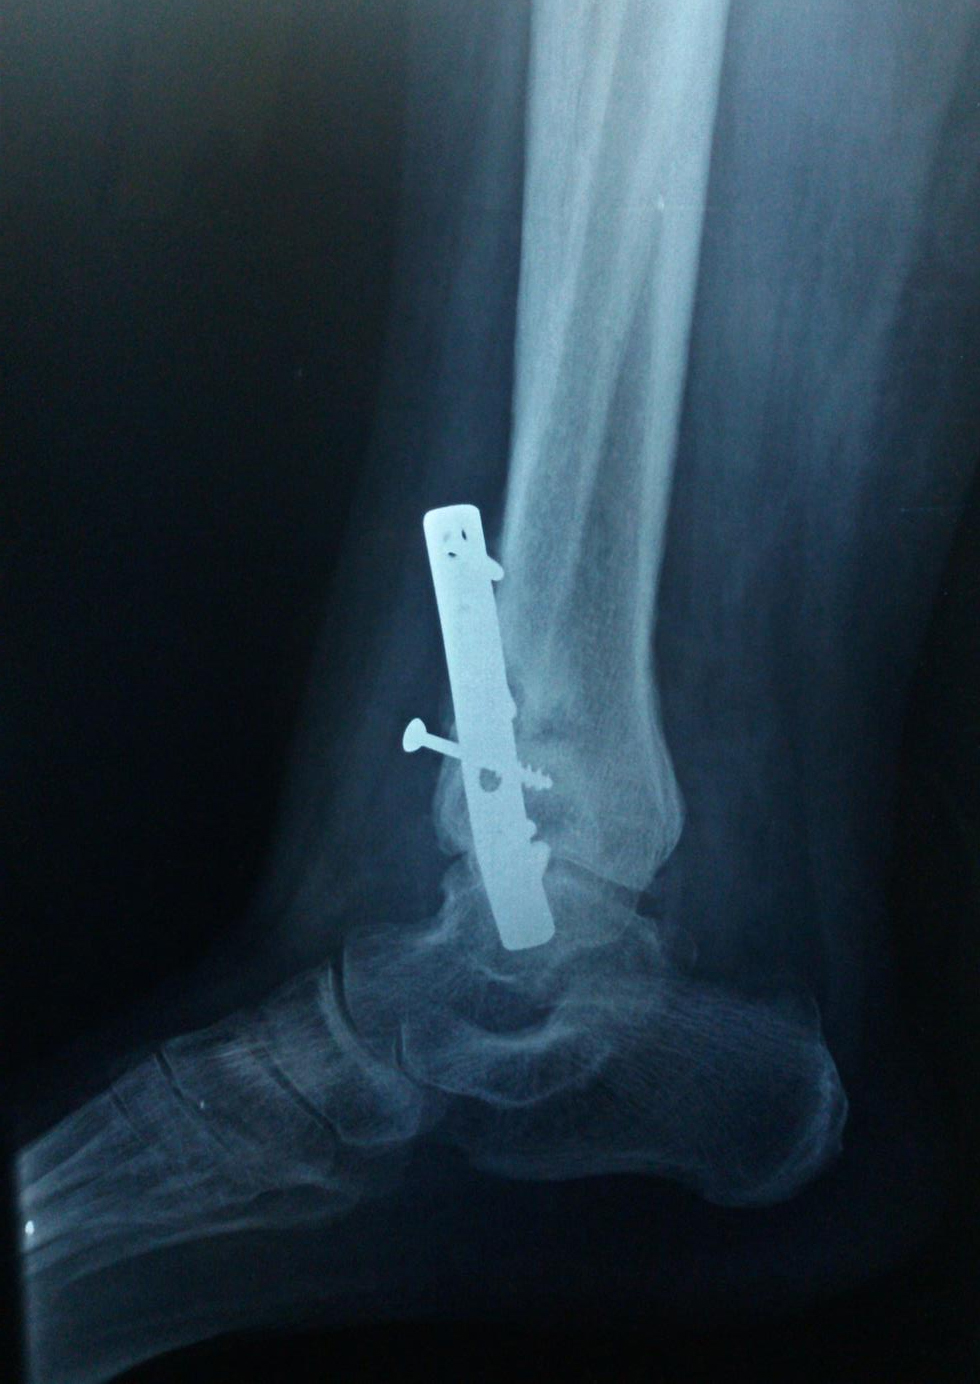

Ankle Fractures Trauma Foot Discoloration After Fracture Get medical advice as soon as possible if you think you've broken your ankle. It may need treatment to heal properly. If you have a broken foot, you may experience throbbing pain that comes on suddenly or develops gradually. The most common symptoms of a fracture are pain and swelling. A metatarsal fracture occurs when one of the long bones. Foot Discoloration After Fracture.